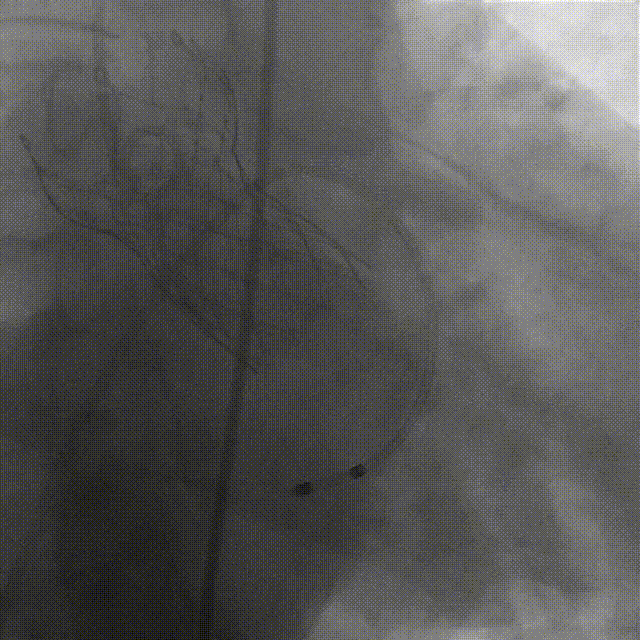

谷兴华教授 山东大学齐鲁医院 锚定终身获益,重视首次干预选择:心脏瓣膜病介入中心成立2年多来,中心核心目标始终保证在解决即刻病症的基础上,护航患者的全生命周期健康管理。 摆在眼前的实际是日益年轻化的患者群体,这意味着我们从手术伊始,就必须将患者未来数十年的生活质量和再次干预风险纳入核心考量,主动规划长远的健康路径。此次患者选择更具耐久的新型干瓣技术,力求减少患者未来再次干预的风险。同时,通过“TAVR+PCI一站式手术”这样的团队协作模式,系统性地处理多重心血管问题,避免分次手术的负担与风险,这正是我们中心一直秉持的“心脏瓣膜病全生命周期管理”理念的实践。让我们一起探索从“治已病”真正迈向“管长远”,让更多的患者获益! 病例特点速览 本次救治的患者,病情呈现“基础病交织、多病变叠加、锚定风险高”三大核心特征。患者为65岁,女性,病变特点TypeI型二叶瓣、轻度钙化,锚定风险大;同时患有冠状动脉粥样硬化性心脏病、慢阻肺(COPD);既往有长期吸烟饮酒史、脑梗死病史、高血压病史、乙肝小三阳病史及腹股沟疝修补手术史,患者STS评分9.32%,外科手术高危,经齐鲁医院瓣膜中心团队评估认为:局麻下“一站式TAVR+PCI”为最优治疗方案,结合患者较年轻,可选择具有长期耐久性的干瓣。 患者病史 主诉:活动后胸闷、憋喘余,加重20余天 既往史:30年前确诊乙肝小三阳,否认其他传染病史;有右腹股沟疝修补手术史,高血压病史,近期规律服药控制。 现病史:患者1年前出现活动后胸闷、憋喘,休息可缓解,为进一步诊治。2月前因“突发意识模糊、口齿不清”于当地医院入院,诊断为“急性脑梗死”,予以微创介入取栓治疗,恢复可,未遗留后遗症。20天前于当地医院再次入院行脑血管支架植入术,术后出现胸闷、憋喘,伴大汗,行心脏超声提示主动脉瓣重度狭窄,并行冠脉造影检查,予以药物治疗。10天前就诊于我院复查心脏超声提示二叶式主动脉瓣,主动脉瓣狭窄(重度)并反流(轻度)。患者现仍感胸闷,双上臂疼痛不适,咳嗽咳痰,日常活动受限。为行进一步治疗就诊于我院,门诊以“主动脉瓣狭窄、冠状动脉粥样硬化性心脏病”收入院; 个人史:吸烟50年,饮酒50年; 体格检查:体温:36℃,脉搏:67次/分,呼吸:18次/分,血压:143/76mmHg; 术前超声提示: 二叶式主动脉瓣主动脉瓣狭窄(重度)并反流(轻度);升主动脉扩张、左心扩大三尖瓣反流(少量);左室充盈异常;CW测最大压差86mmHg,平均压差43mmHg,最大血流速度463cm/s,连续方程法估测主动脉瓣口面积0.78cm² 术前CT评估 Type1型二叶瓣,轻度钙化、左右融合,主动脉瓣环径25.3mm,LVOT直径25.5mm,鱼嘴空间约26.6mm,主要靠瓣环锚定。窦部空间大、左右融合,VTC空间足够,无冠脉风险 ;左室内径正常,主动脉瓣环水平夹角49.6°。外周双侧入路内径可,髂外动脉存在散在钙化、双侧入路能够支持20F大鞘通过,右股低分叉,主动脉弓距弓角可。 个性化手术策略:局麻一站式方案+创新瓣膜精准适配 入路选择:主入路:右侧股动脉(右股分叉上方1cm处穿刺);辅入路:左侧股动脉;器械:20F大鞘; 手术流程规划:局麻下行同期一站式TAVR+PCI,植入ProStyle A®预装干瓣; 瓣膜选型与预处理:瓣膜型号:ProStyle A® AV32;不预扩; 定位与释放方案:初始定位:瓣上3mm处释放,瓣膜自然下滑至工作位,最终目标“0-瓣下5mm位”。 手术过程:局麻一站式操作+创新瓣膜植入,无缝衔接 手术团队按预设方案稳步推进,实现TAVR、PCI与ProStyle A®干瓣植入的无缝衔接: 1.术前准备:完成影像评估、血管通路建立,确认ProStyle A® AV32瓣膜状态; 2.PCI治疗:通过主入路完成左冠造影,前降支、对角支明显狭窄,精准植入两枚支架,恢复冠脉血供; 左冠造影,前降支、对角支病变 PCI后造影,病变血管充盈良好 3.主动脉根部造影:确认主动脉根部解剖结构,并精准跨瓣; 主动脉根部造影 精准跨瓣 4.干瓣植入:将瓣膜输送过弓、过瓣,并精准定位; 输送系统柔顺过弓 精准定位 5.术中评估:释放瓣膜至工作状态,再次造影评估,位置满意,完全释放瓣膜; 工作位评估 32号瓣膜稳定脱钩 6.释放后造影:可见瓣膜位置满意、形态良好,无明显瓣周漏。 最终造影,位置形态良好,无瓣周漏 术后超声探查:位置(瓣下4mm)、形态良好,无瓣周漏,PGmean=10mmHg。 此次手术的成功,体现了山东大学齐鲁医院心脏瓣膜病介入中心秉承的“心脏瓣膜病全生命周期管理”的理念和团队协作的临床能力。面对低龄高风险复杂病例,团队通过术前充分评估、术中精细操作,结合具有长期耐久性的干瓣技术,以一站式方案改善患者症状、提高生活质量并延长寿命,为类似病例的诊疗提供宝贵经验。 专家简介 谷兴华 山东大学齐鲁医院(点击查看专家详细简历)